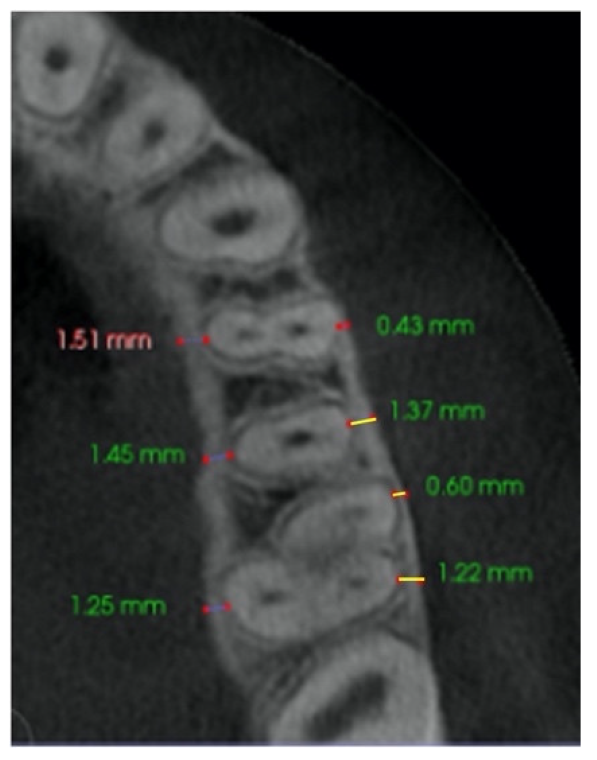

| Buccal bone thickness (BBT) | Distance from the external border of the buccal cortical plate to the center of buccal aspect of first and second premolar root, and from the external border of buccal cortical plate to the center of the messiobuccal and distobuccal root of first molar, in an axial section parallel to the palatal plane, at the level of the first molar right (R) and left (L) trifurcation for each side. | ![]() ![]() |